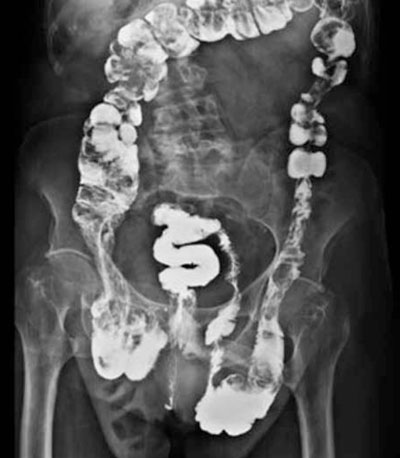

Hernia inguino escrotal bilateral, irreductible. A nivel de la hernia izquierda se palpó una tumoración pétrea, de 2 por 2 cm aproximadamente, móvil, no dolorosa. Testículo y cordón de características normales. Examen proctológico: no se palparon tumoraciones. Se realizó una ecografía de partes blandas que informó lesión compatible con tumor de colon. Con planteo de cáncer de colon se solicitó un colon por enema que evidenció una lesión estenosamente del sigmoides en la hernia (figuras1y2). Resto del estudio normal.

Figura 2: Colon por enema. Imagen de sustracción en colon sigmoides contenido en la hernia izquierda.